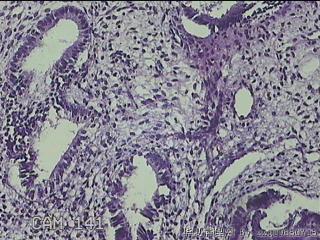

子宫腔内容物

性别

女

年龄

31

临床诊断

宫腔息肉?

一般病史

宫内异常回声2月余。

标本名称

大体所见

灰白暗红色不规则碎组织2x1.7x0.3cm一堆.

图1